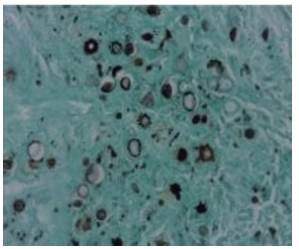

Las tinciones de rutina para realizar la histopatología son la hematoxilina- eosina, junto con el PAS y el Grocott o plata metenamina, que constituyen las tinciones básicas para el estudio de las micosis. Hay también tinciones opcionales como la de Fontana-Masson para el estudio de pigmento melánico, importante en las feohifomicosis y las tinciones para mucipolisacáridos, como la de mucicarmin, básicas para el estudio de Cryptococcus spp y otros hongos que en su pared o cápsula contengan glucoproteínas (figura 4 y 5).

El patólogo, una vez procesada la muestra, puede observar bajo el microscopio las diferentes estructuras micóticas tales como hifas y esporas o conidias, pigmentadas o no. Conociendo los cambios tisulares que se producen en los tejidos y las diferentes morfologías puede llevar a clasificarlos y ofrecer un diagnóstico 25-27.